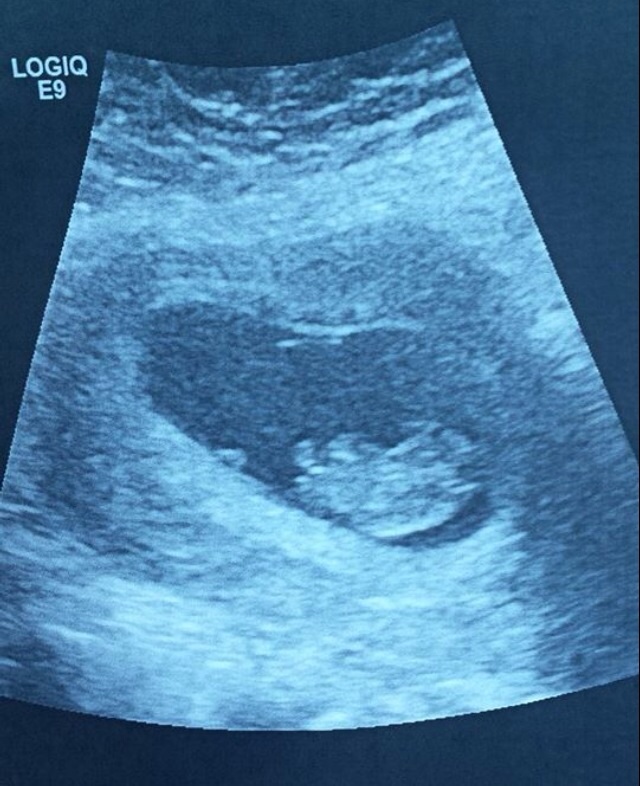

We are both absolutely healthy. Measuring perfectly and happy healthy bouncing bean